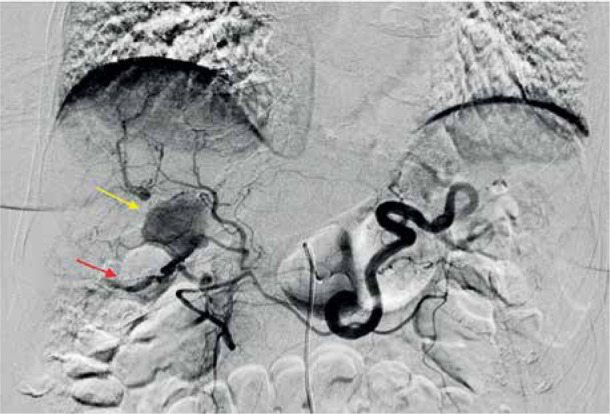

一名系统性红斑狼疮血管炎患者的右肝动脉分支肝内动脉瘤。

Intrahepatic aneurysm in a branch of the right hepatic artery in a patient with vasculitis due to systemic lupus erythematosus.